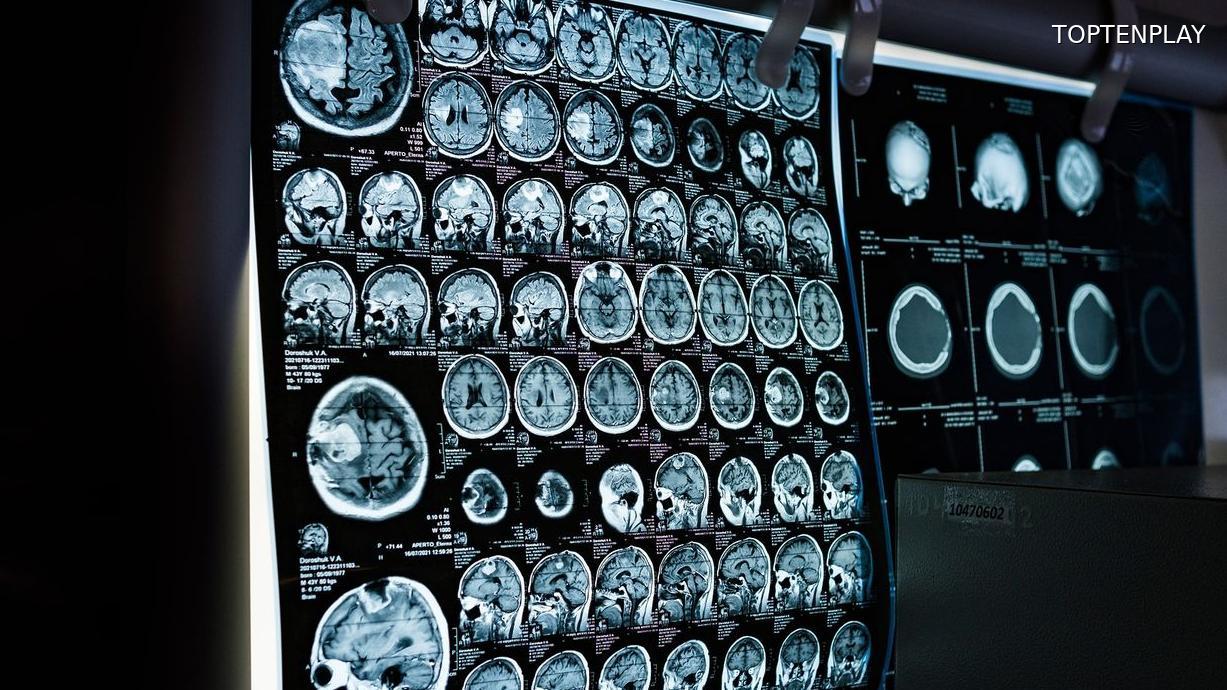

Aux urgences, la batterie d’examens a révélé l’ampleur du danger. La tumeur, de la taille d’un œuf, était localisée à l’arrière du tronc cérébral et exerçait une pression critique sur le cerveau de Nyo. Face à cette urgence vitale, les médecins ont agi immédiatement : un drain a été posé pour évacuer le liquide céphalo-rachidien et soulager cette compression mortelle.

Cinq jours plus tard, le 10 décembre, l’enfant entrait au bloc opératoire. L’intervention chirurgicale a duré neuf heures. Une opération d’une complexité extrême, menée avec succès : la tumeur a été entièrement retirée. Les tests réalisés après l’opération ont apporté un premier soulagement : aucune métastase n’a été détectée.

Si l’urgence vitale est écartée, l’inquiétude demeure. Une IRM a été réalisée pour détecter d’éventuelles cellules cancéreuses résiduelles. Les résultats, toujours attendus, détermineront la suite du traitement de Nyo. Cette période d’attente pèse lourdement sur ses parents, confrontés à une question lancinante : « Nyo sera-t-il toujours le même ? »